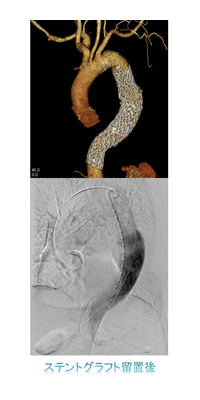

Hybrid OR

Hybrid ORは手術台とIVR(インターベンショナルラジオロジー)の行える血管撮影装置を組み合わせた手術室のことです。Cアームスタンドの6軸とコリメータ、FPD(フラットパネルディテクタ)の回転機構を加えた計8軸の回転機構から構成されているロボットアーム型の血管撮影装置を搭載しており、多彩なCアーム挿入ポジションを選択でき、術者の妨げにならずに手技を行うことが可能であります。

ハイブリット手術室では経皮的大動脈弁置換術(TAVI)、経皮的僧帽弁クリップ術(MitraClip)、左心耳閉鎖術(WATCHMAN)などの構造的心疾患(SHD:Structure Heart Disease)に対するインターベンションをはじめ、大動脈解離や大動脈瘤に対するステントグラフト内挿術(TEVAR、EVAR)、エキシマレーザーを用いたデバイスリード抜去術など、様々な手技を行っています。

従来は開胸や開腹して行っていた手術や、高齢やリスクが高いことが原因で治療ができなかった患者さんに対して開胸せずに低侵襲なカテーテル治療を行うことができるようになりました。